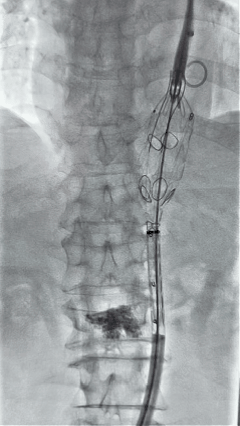

3. 经右股动脉导入超硬导丝,然后导入先健G-Branch 胸腹主动脉主体覆膜支架TAAA3418120e7i1010 一枚,释放主体支架至内分支打开,然后经左侧肱动脉入路,抓捕预置导丝成功后,将长鞘进入内分支出口处。

4. 经长鞘导入导管后,超选入腹腔干动脉,送入先健覆膜支架10*80mm一枚,近端重叠内分支,远端重叠腹腔干动脉,并予以10mm球囊后扩,手推造影显影良好。

5. 撤出腹腔干导丝导管,经左肱动脉长鞘继续抓捕预置导丝将长鞘超选至另一侧内分支,后超选进肠系膜上动脉,沿导丝送入先健覆膜支架10*100mm一枚,近端重叠内分支,远端重叠于肠系膜上动脉,并予以10mm球囊后扩,手推造影显影良好。